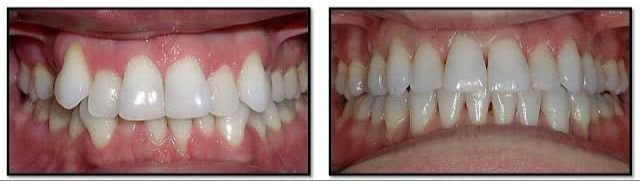

MOST POPULAR TREATMENTS

What we offer